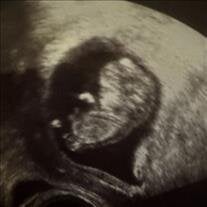

Baby Evan Lee Parson

June 7, 2025 - June 7, 2025

With broken hearts and everlasting love, we share the passing of our precious baby boy, Evan Lee Parson, who was born and passed away on June 7, 2025, at Midland Memorial Hospital in Midland, Texas. Evan was lovingly welcomed into the world... View Obituary & Service Information